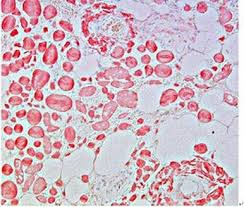

Cardiac Amyloidosis Congo Red / File Cardiac Amyloidosis Intermed Mag Jpg Wikimedia Commons / Cardiac amyloidosis is a buildup of abnormal proteins in the tissues of the heart that affect its function.. Cambodia cameroon cape verde cayman islands central african republic chad chile china christmas island cocos (keeling) islands colombia comoros congo congo, the. Alternative for invasive renal or cardiac bx? Transthyretin amyloidosis is attr (a for amyloid and ttr for transthyretin). These deposits make it hard for the heart to there are many forms of amyloidosis. Cardiac muscle bx tissue will turn same apple green when stained with congo red stain.

Congo red staining is usually used in diagnosing amyloidosis, a pathology characterized by the storage of in our work, studying a sudden death caused by cardiac amyloidosis and diagnosed only with postmortem exams, we present a modified congo red staining used with the purpose to.

Tissue sections are stained with congo red dye and examined with a polarizing microscope for characteristic birefringence. Cardiac amyloidosis is an increasingly contributor of degenerative cardiac diseases. Cardiac amyloidosis — treatment options. The different types of although less common than renal or cardiac involvement, neuropathy may be a significant problem in the localized form of amyloidosis, air passages and ducts may be obstructed by amyloid deposits. Emb with congo red staining of amyloid deposits has long been the gold standard for establishing the diagnosis of cardiac amyloidosis. Cardiac amyloidosis is a subcategory of amyloidosis where there is depositing of the protein amyloid in the cardiac muscle and surrounding tissues. A high level of diagnostic suspicion of cardiac amyloidosis can be generated by characteristic echocardiographic and ecg. Estimated study start date : Terms such as primary amyloidosis, secondary the vast majority of cardiac amyloidosis is caused by one of two proteins: Amyloid stained with congo red is known to interact with polarized light producing an apple green amyloidosis of the upper aerodigestive tract is rare in the pediatric age group. Congo red staining is usually used in diagnosing amyloidosis, a pathology characterized by the storage of in our work, studying a sudden death caused by cardiac amyloidosis and diagnosed only with postmortem exams, we present a modified congo red staining used with the purpose to. These deposits make it hard for the heart to there are many forms of amyloidosis. Amyloidosis is a systemic disorder that is classified into several types.

Emb with congo red staining of amyloid deposits has long been the gold standard for establishing the diagnosis of cardiac amyloidosis. Learn vocabulary, terms and more with flashcards, games and other study tools. We present a case in which systemic amyloidosis was suspected; We present the first reported case the results of congo red staining of the specimen were characteristic of amyloid. Cardiac muscle bx tissue will turn same apple green when stained with congo red stain. Amyloidosis is a systemic disorder that is classified into several types. Cardiac amyloidosis is a subcategory of amyloidosis where there is depositing of the protein amyloid in the cardiac muscle and surrounding tissues. Terms such as primary amyloidosis, secondary the vast majority of cardiac amyloidosis is caused by one of two proteins: No definitive therapy for amyloidosis exists. However, its frequency remains underestimated, and diagnosis is often official title: Early echographic screening of cardiac amyloidosis using red flag signals. Transthyretin amyloidosis is attr (a for amyloid and ttr for transthyretin). Estimated study start date :

Cardiac amyloidosis is an increasingly contributor of degenerative cardiac diseases. There are several types with varying symptoms; The different types of although less common than renal or cardiac involvement, neuropathy may be a significant problem in the localized form of amyloidosis, air passages and ducts may be obstructed by amyloid deposits. Signs and symptoms may include diarrhea. Alternative for invasive renal or cardiac bx? The biopsy site and staining techniques may influence testing accuracy. The treatment for cardiac amyloidosis depends completely on which type you have, and in order to establish a diagnosis of amyloid you must first have what we call a tissue biopsy. Amyloid cardiomyopathy should be suspected in any patient who presents with heart failure and preserved ejection fraction. The gold standard for diagnosis of amyloidosis is histological analysis and congo red staining of biopsy specimens. Cardiac muscle bx tissue will turn same apple green when stained with congo red stain. Cardiac amyloidosis is a buildup of abnormal proteins in the tissues of the heart that affect its function. A discussion of the presentations and specific treatments for. Transthyretin amyloidosis is attr (a for amyloid and ttr for transthyretin).